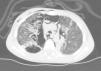

Thoracic radiography revealed thickening of the interstitial pattern, multiple radiotransparent areas due to the interstitial emphysema and parenchymatous opacities in the left middle and lower lung fields. Thoracic computed tomography revealed diffuse pneumomediastinum with subcutaneous emphysema (Fig. 1).